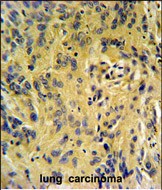

- TESC Antibody (C-term) (Cat. #P30635) IHC analysis in formalin fixed and paraffin embedded human lung carcinoma followed by peroxidase conjugation of the secondary antibody and DAB staining. This data demonstrates the use of the TESC Antibody (C-term) for immunohistochemistry. Clinical relevance has not been evaluated.